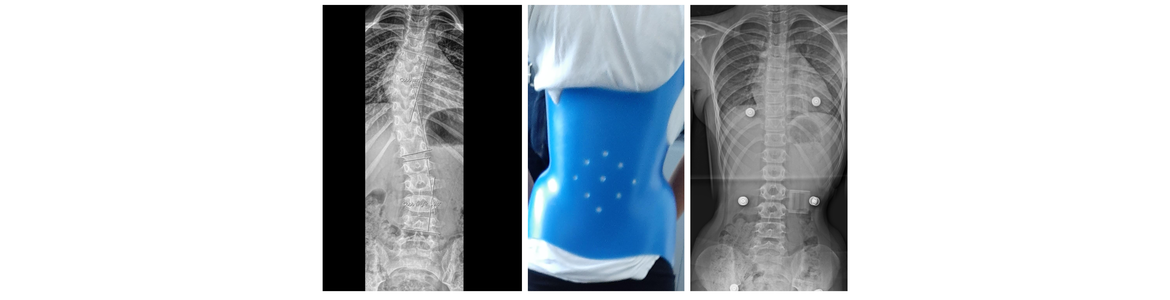

Ραιβοϊπποποδία

Εγκεφαλική Παράλυση

Το παραπάνω κορίτσι διαγνώστηκε με εγκεφαλική παράλυση. Περπατούσε στα άκρα των ποδιών και τα δύο πόδια περιστρέφονταν εσωτερικά.

Το κορίτσι που φαίνεται παρακάτω υπέστη πολυεπίπεδη χειρουργική επέμβαση για εγκεφαλική παράλυση. Εδώ παρουσιάζεται σε διάστημα ενός έτους μετά τη χειρουργική επέμβαση.